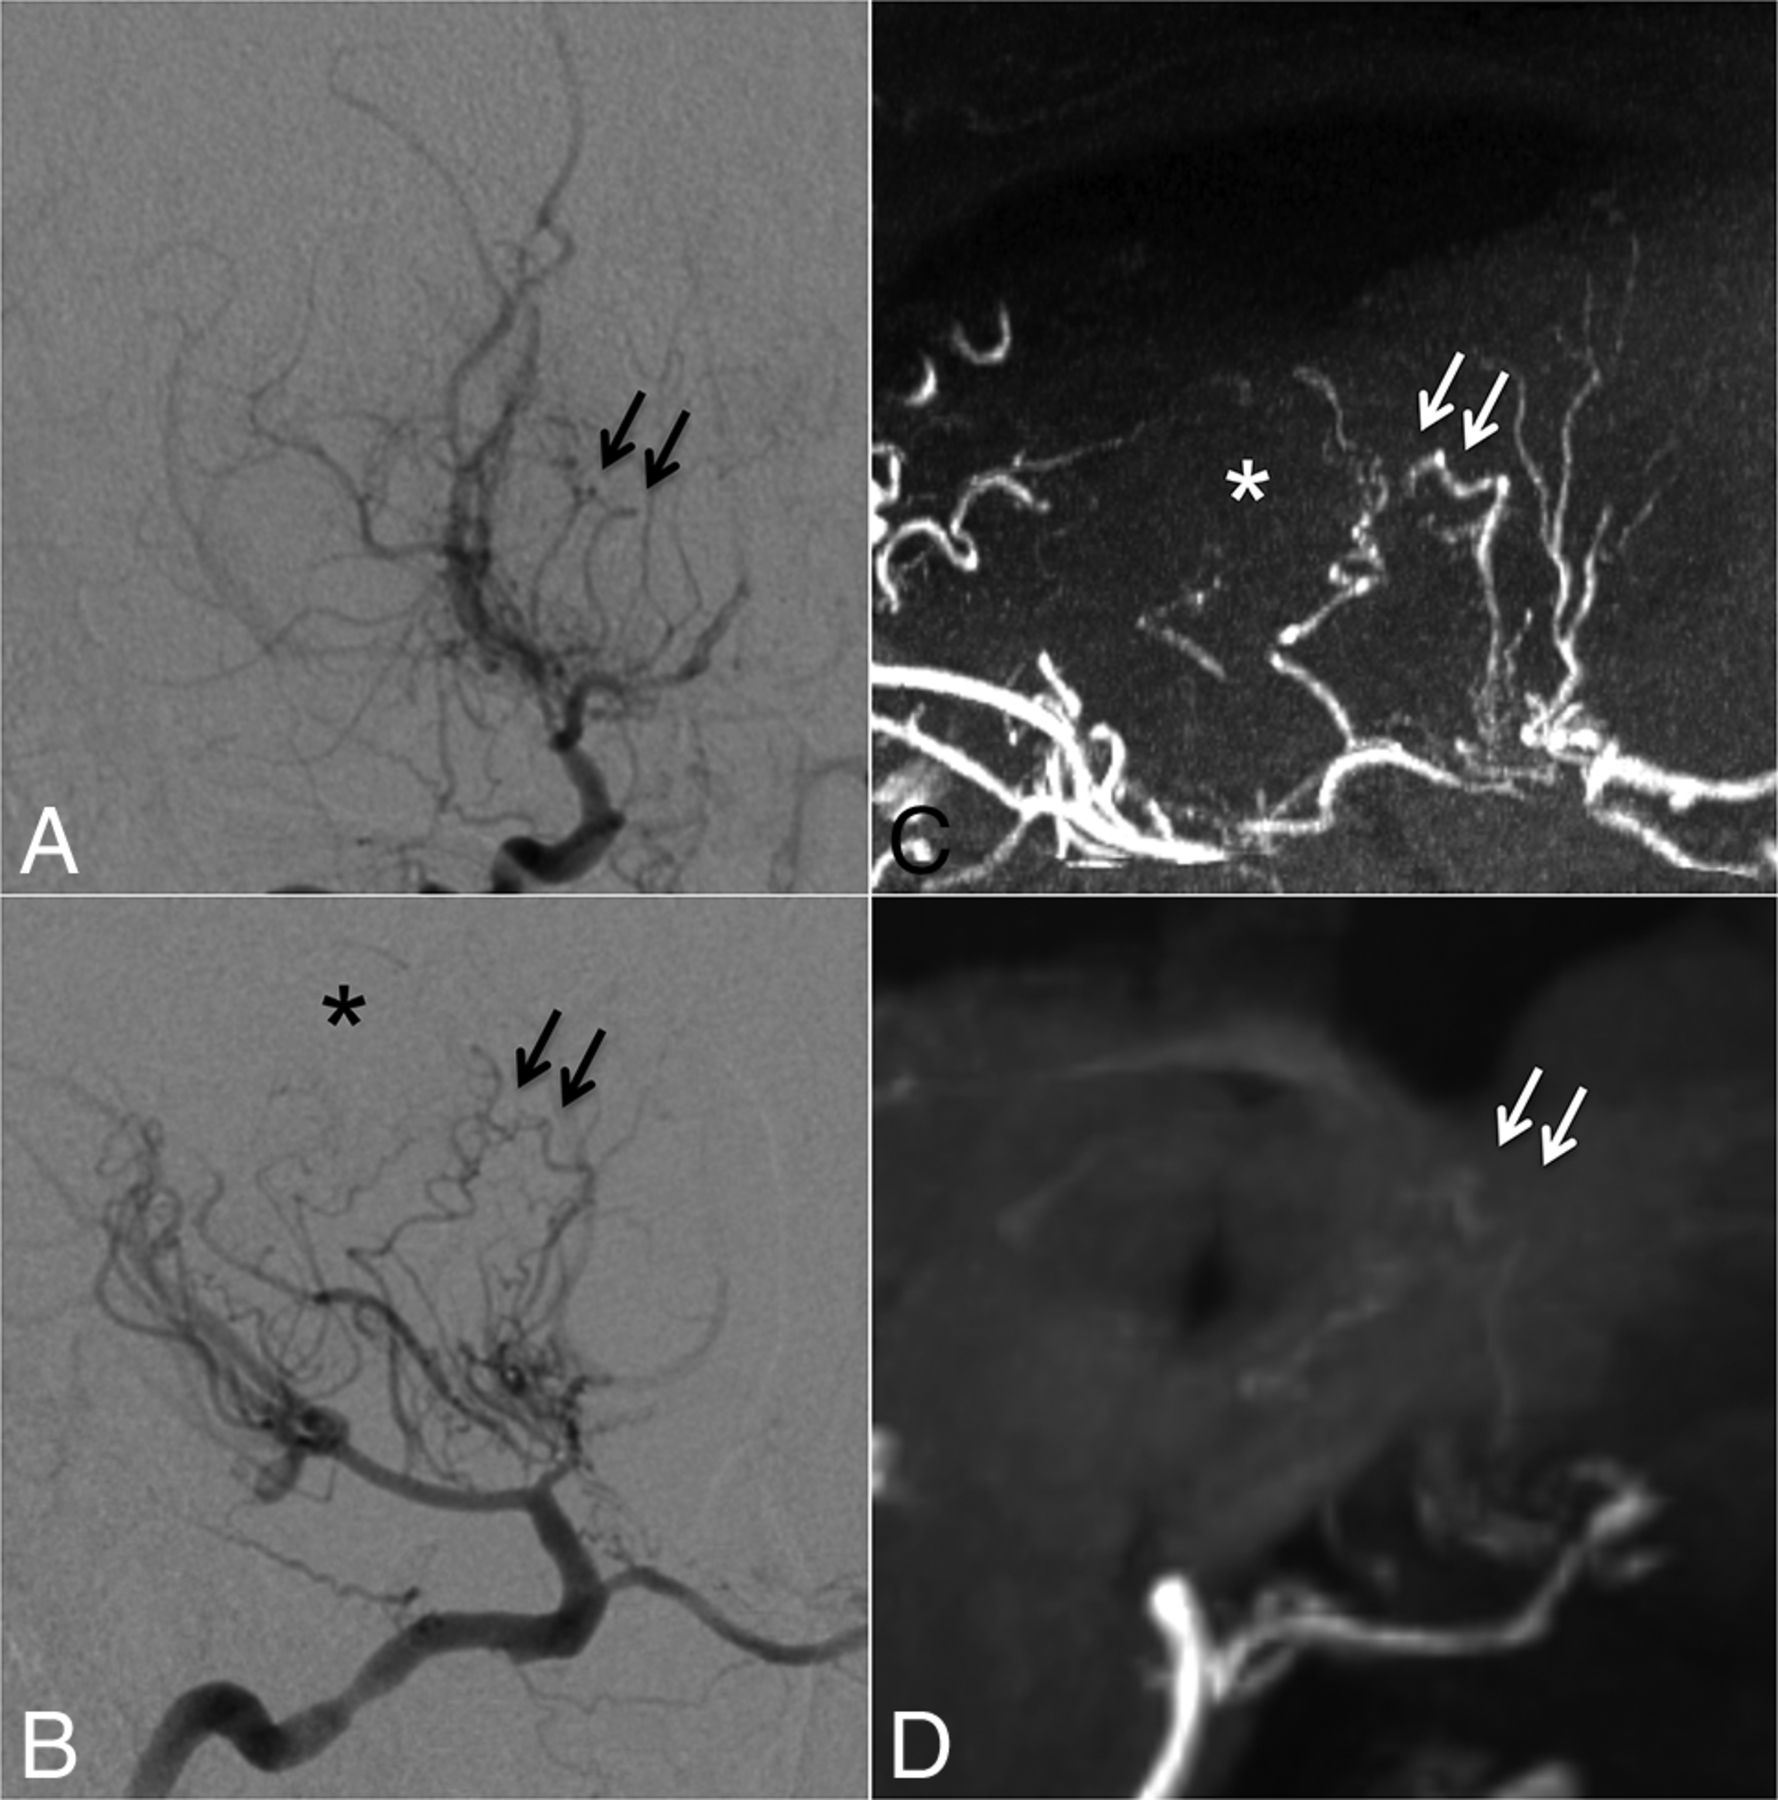

Collateral networks among major trunk vessels (MCA, anterior cerebral artery, choroidal arteries, and communicating arteries) were also identified as having a U-shaped running course. Especially, anastomoses between either choroidal arteries or the posterior communicating artery and thalamostriate arteries were located in the basal ganglia running adjacent to the ventricles (type c: Fig 3). Intrastriatal anastomoses among striatal arteries were prominent in the basal ganglia (type d: Fig 4). Intrathalamic anastomoses among thalamic arteries from posterior cerebral arteries were relatively rare (type e: Fig 5). Anastomoses among Moyamoya vessels focally proliferated in the basal cistern were detected in all patients (type f: Fig 4).

Case 5. Selective right internal carotid angiography (right 45° oblique, A; left 45° oblique view, B) shows intrastriatal anastomoses among thalamostriate arteries running through the periventricular space (arrows, type d). MIP from TOF-MRA (C) excellently demonstrates these networks as well as focal connections among Moyamoya vessels in the basal cistern (asterisk, type f). MIP from MPRAGE (D) moderately depicts the network; however, basal Moyamoya vessels are poorly visualized.

Case 6. Selective left vertebral angiography (anteroposterior, A; lateral view, B) shows no marked anastomosis. The MIP from TOF-MRA (C) demonstrates excellent visualization of inner thalamic anastomosis among posterior thalamostriate arteries (white arrows, type e), whereas the visualization is only moderate on MIP from MPRAGE (D).